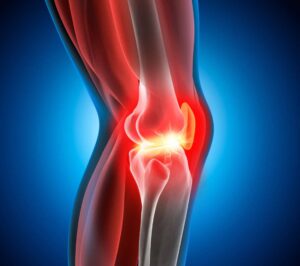

Die Orthopädie ist ein medizinisches Fachgebiet, das sich mit der Prävention, Diagnose und Behandlung von Erkrankungen und Verletzungen des Bewegungsapparates beschäftigt. Knochen, Gelenke, Muskeln, Sehnen und Bänder müssen gemeinsam funktionieren, um uns Beweglichkeit und Stabilität zu ermöglichen.

Auf unserer Seite finden Sie umfangreiche Informationen zu orthopädischen Beschwerden und Erkrankungen. Von der Arthrose über Bandscheibenvorfälle bis hin zu Kreuzbandriss und weiteren Sportverletzungen: wir geben Ihnen einen Überblick über die häufigsten orthopädischen Krankheitsbilder, wie sie behandelt werden können und inwieweit ein Bildgebungsverfahren, wie eine (z.B. MRT Knie, Rücken MRT) bei der Diagnose bei der Diagnose unterstützend wirken können.

Unsere Liste zu den häufigsten orthopädischen Problemen ist alphabetisch von A-Z geordnet. So finden Sie schnell und unkompliziert den Beitrag, der Ihnen weiterhilft. Von Krankheiten, über Verletzungen bis hin zu schmerzhaften Zuständen wie Arthrose, Meniskusschaden und Schleimbeutelentzündung – hier finden Sie die wichtigsten Informationen.